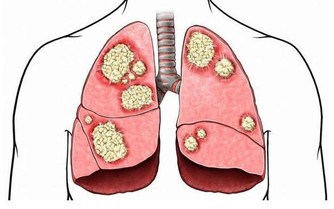

7.硒:可形成特殊蛋白有助於防止細胞損傷

特別提醒:可能會降低某些癌症的風險,如肺癌、結腸癌和前列腺癌。